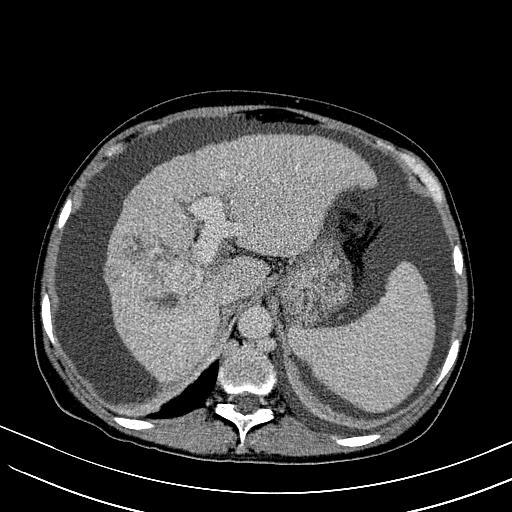

标题: CT23697:肝癌并肝动静脉漏? [打印本页]

标题: CT23697:肝癌并肝动静脉漏?

肝动静脉漏,动脉期肝动脉及门静脉内均可见造影剂……

1)肝右叶肝癌并肝动静脉漏。2)肝硬化,腹水。3)胆囊炎。

肝右叶肝癌并动静脉漏,肝硬化,腹水。

1)肝右叶肝癌并肝动静脉漏 门v右支瘤栓伴海绵样变。2)肝硬化,脾大 腹水。3)胆囊炎。门v高压.

右叶肝癌并肝动静脉漏(动脉期肝动脉及门静脉内均可见造影剂),肝硬化,腹水。(胆囊壁水肿)

1)肝右叶肝癌,考虑并发肝动静脉漏。扫描时间好像慢了。2)肝硬化,门脉高压、脾大、腹水。